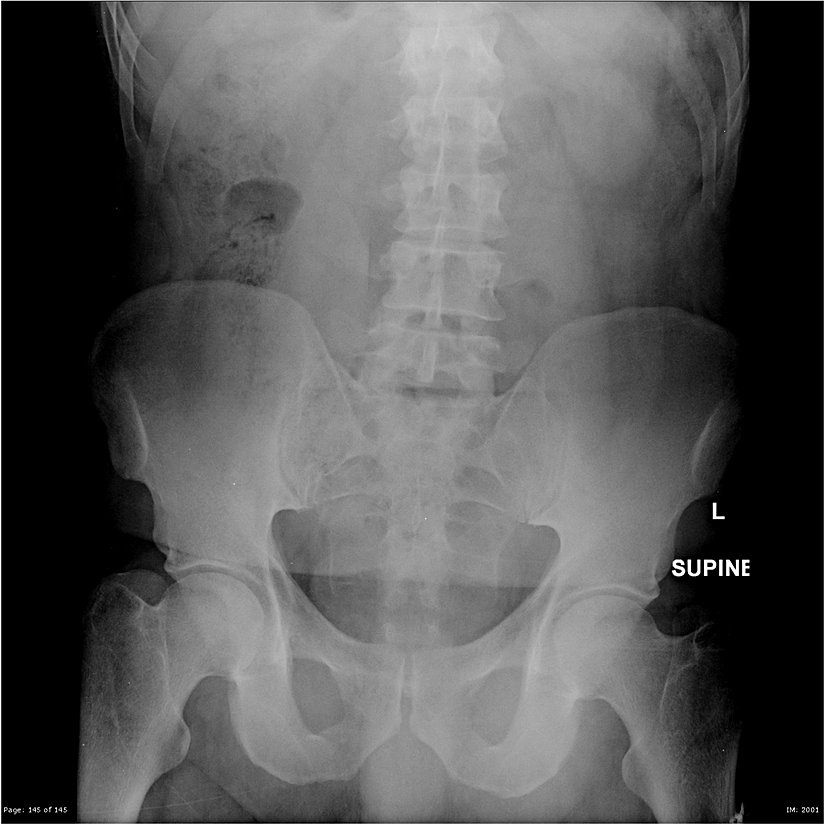

50 yaşındaki erkek bir çiftçi, çiftçi, yoğun karın ağrısı ile hastaneye kaldırılmıştır. Öncelikle gaz birikimi olduğu düşünülmüş; ancak yapılan incelemeler, bağırsak gaz örüntülerinin karın içerisinde birikmiş bir gaz belirtisi olmadığını göstermiştir. Frontal X-Işını taraması yapıldığında, vücutta hekimi ikna edici düzeyde intrabdominal gaz olmadığı görülmüştür. Tarama görüntüsü aşağıdan görülebilir: